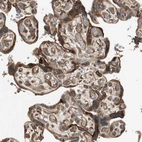

Immunohistochemical staining of human placenta shows strong cytoplasmic and membranous positivity in trophoblastic cells.